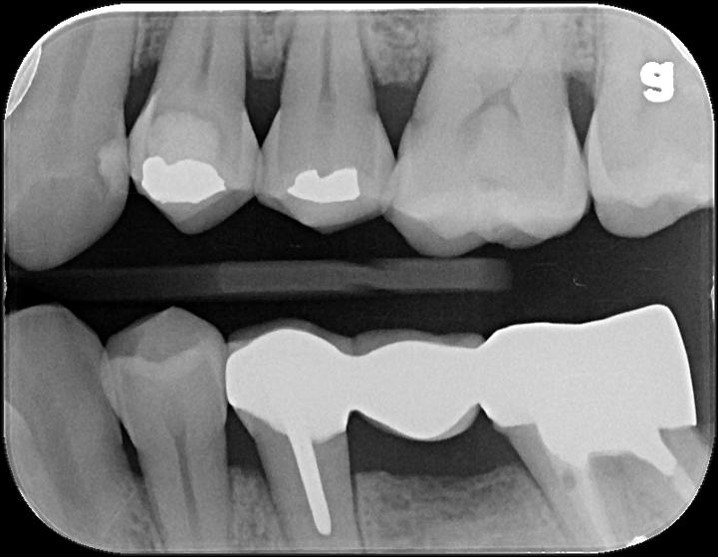

治療前,銀粉導致滲透

蛀牙未至牙髓